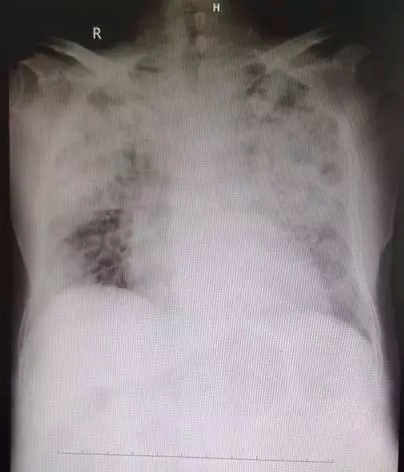

经历了腹部和胸部的两个大手术后,老先生被送进了重症监护室。在里面又发生房颤,心率上升到150以上,血象一度高达3万。其间,董鹏又就转复房颤等问题一一与管床大夫沟通。终于,在第六天,父亲情况略微好转,从三院转院到航空总医院继续治疗。此时的胸片显示,两肺白花花一片,在向中日医院呼吸与危重症医学詹庆元教授请教后,初步诊断为曲霉菌肺炎,用上了抗生素治疗。

治疗前的肺部影像